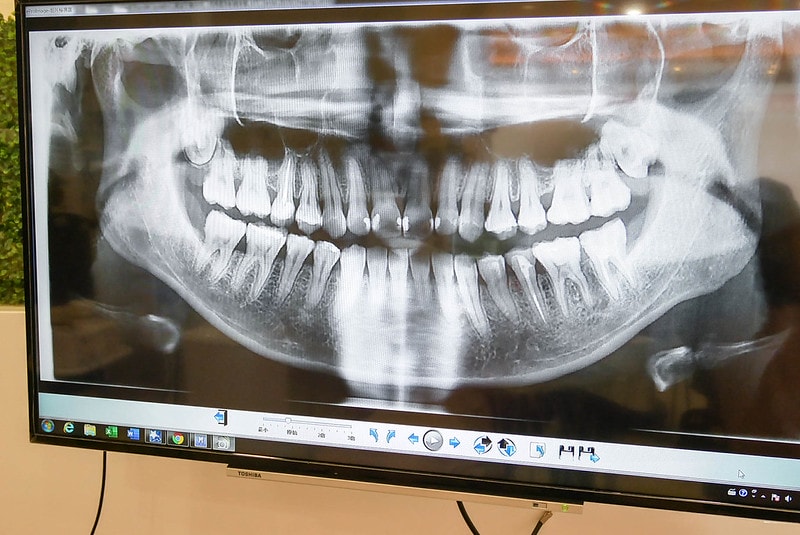

接下來的流程是拍X光和口內彩色照

由醫師解說牙齒的情況與諮詢建議

醫師會花較多時間了解需求及說明可改善的狀況

哈哈 看到自己牙齒的X光片突然覺得有點害羞

真的是常常一直在蛀牙

也有幾顆做過根管治療

牙齒真的是平常就該好好保養

不然一花錢都是大筆的~XD